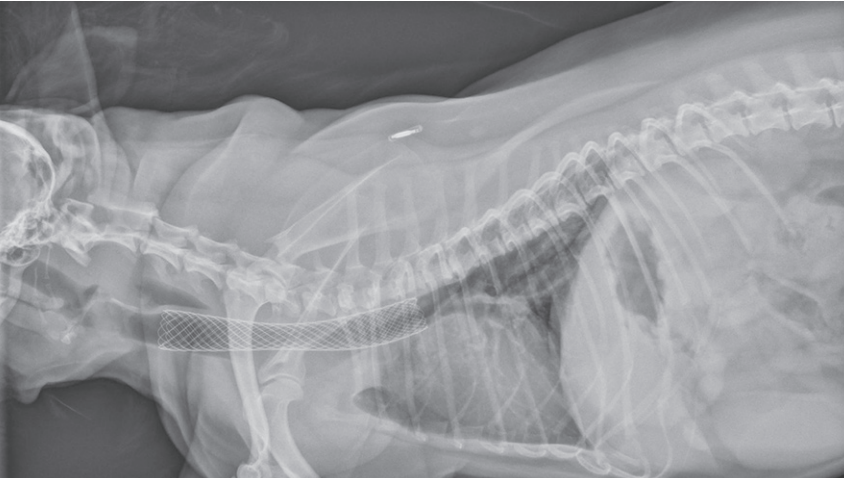

- 氣管支架置入:透過內視鏡將金屬自膨式支架送入塌陷段,立即恢復氣道通透,適用於藥物治療效果不佳的病例。

治療方式(外科手術):對於像這樣病情嚴重、靠藥物控制效果不佳,甚至已經出現呼吸衰竭風險的狗狗來說,氣管支架置入術就是一個很重要的選項。

術後成果:狗狗放入氣管支架後的X光片(如圖二),可以看到氣管已經被撐開了,呼吸終於順暢許多!放了支架之後,通常還是需要長期搭配藥物來控制炎症或感染,絕對不是放了支架就萬事OK,還是要持續觀察追蹤。